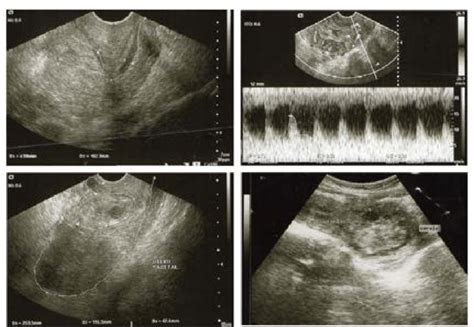

Se presenta el caso de una paciente de 31 años, en su segundo embarazo (30.2 semanas de gestación), con antecedente de cesárea previa. Acudió al servicio médico por presentar salida de líquido transvaginal, confirmándose la ruptura prematura de membranas pretérmino (RPM) mediante cristalografía y la prueba de Amnisure®. La valoración médica reveló placenta previa total con características de acretismo placentario (lagunas placentarias, flujo turbulento, grosor miometrial < 1 mm y pérdida de la interfase deciduomiometrial).

Caso Clínico: Hemorragia Posparto por Placenta Previa Oclusiva

Otro caso presentado es el de una mujer de 39 años, secundigesta, con antecedente de cesárea previa, quien acudió a las 31+1 semanas de gestación por metrorragia escasa. Se diagnosticó placenta previa oclusiva, iniciando maduración pulmonar fetal. Al día siguiente, presentó sangrado vaginal muy abundante, lo que llevó a una cesárea urgente para la extracción de un feto de 1.015 g.